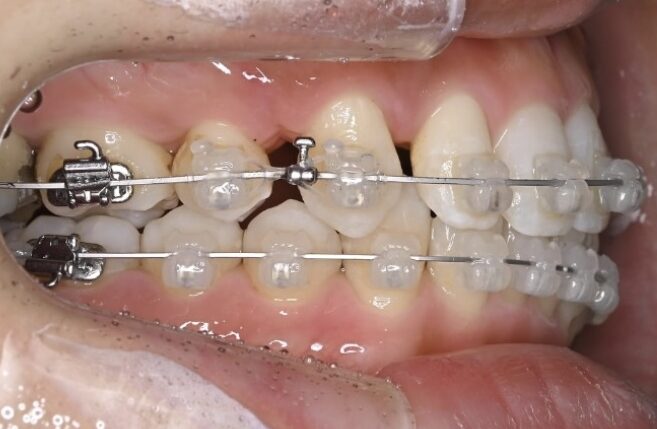

治療経過(半年後)

治療開始から半年ほどで、前歯の重なりは徐々に改善し、清掃性も向上してきました。患者さま自身も「磨きやすくなった」と実感されています。